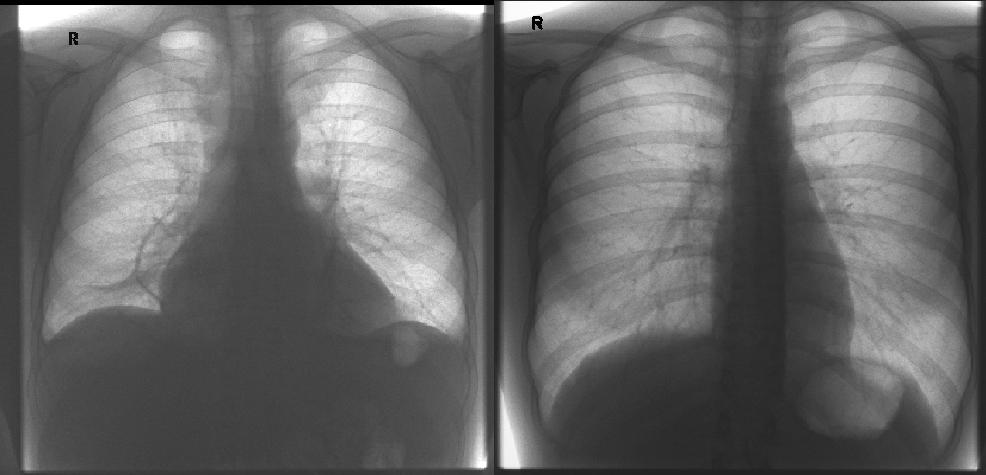

⭕ A 45-year-old male presents with progressive dyspnea, orthopnea, and pedal edema for 3 months. Chest X-ray comparison is shown. The right image shows a normal cardiac silhouette, while the left image shows an enlarged globular cardiac shadow. What is the most likely diagnosis